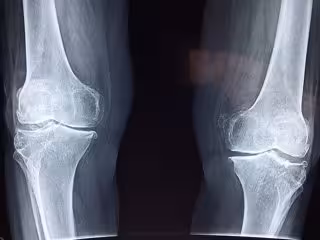

Archivo - Radiografía rodilla

Archivo - Radiografía rodilla - TAOKINESIS /PIXABAY - Archivo